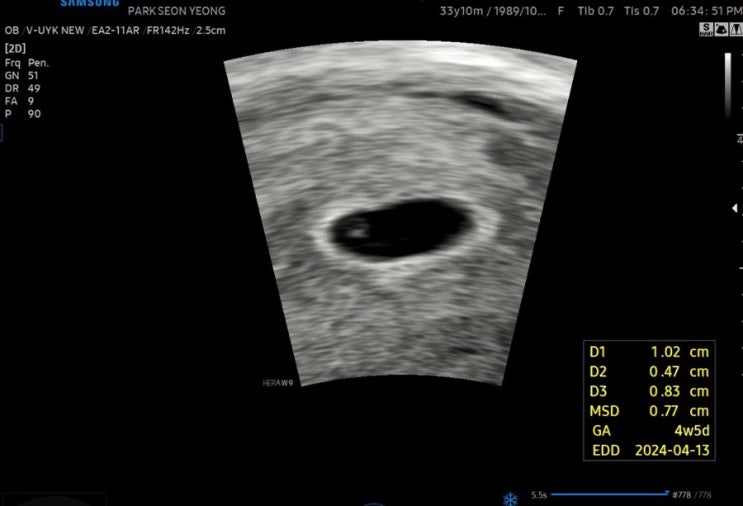

[임신일기]임신2주차~임신9주차증상/경산모

출산/육아 카테고리에 다시 출산일기를 쓰게되다니.. 둘째가 찾아왔다 웅 사람둘째 실질적으로 꼬리까지 포...